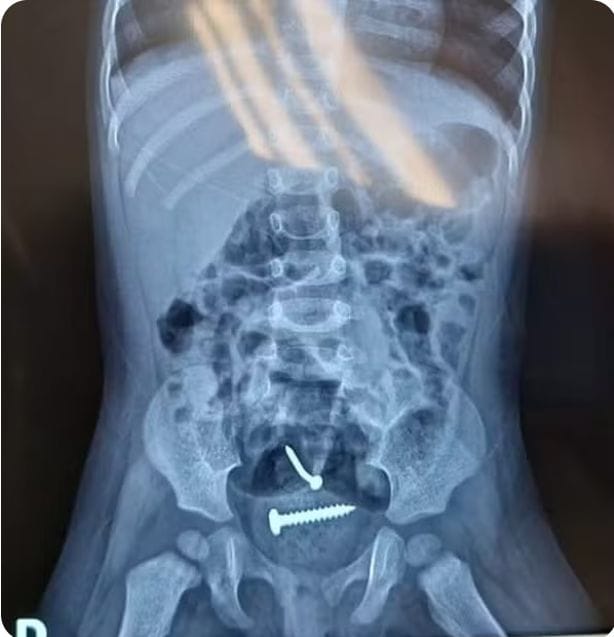

Médicos encontram parafusos dentro de criança suspeita de sido violentada pelo pai no Piauí — Foto: Divulgação/PM-PI

De acordo com a Polícia Militar, o caso foi denunciado pelo hospital para onde as vítimas foram levadas. Ao chegar na unidade, um raio-X apontou a presença de objetos estranhos no corpo da criança, que também apresentava lesões nas partes íntimas.